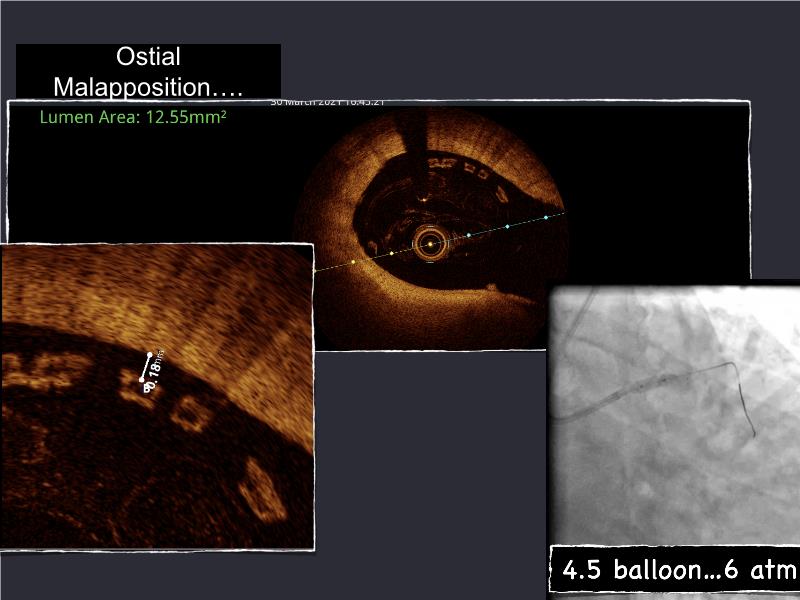

- To understand novel tools and techniques for effective management of bifurcation lesions and long diffused lesions using dedicated stenting solutions